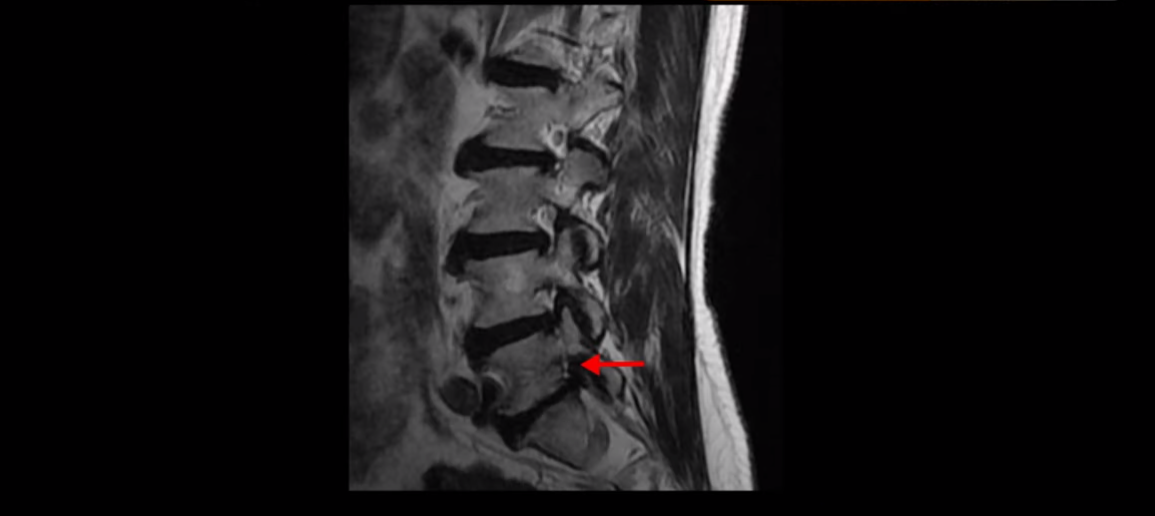

먼저 이분 MRI 보면서 간단히 설명 드린 후 어떻게 신경이 눌려서 수술해야 된다는 환자를 수술 없이 치료할 수 있는지 또 치료는 어떻게 하는지 자세히 설명 드리겠습니다. 이분 허리 MRI를 보면 여러 마디가 퇴행되어 있고

3번 4번 마디에 디스크 파열이 있습니다.

하지만 이 디스크 파열은 오래된 걸로 보이며, 지금 이 환자분의 아픈 양쪽 다리 특히 양쪽 발의 통증, 발 시린 증상과는 관련이 없어 보입니다. 오른쪽 왼쪽의 신경가지가 빠져나가는 추간공을 보면 오른쪽은 5번 1번과 4번 5번이 많이 좁아져 있고

왼쪽은 5번 1번이 많이 좁아져 있습니다.

이렇게 오른쪽 왼쪽 양쪽 추간공들이 다 좁아져 있고 신경가지들이 눌려있으니까 양쪽다리와 양쪽 발이 저리고 시리고 아파서 걷기 어렵습니다. 그런데 이 환자분은 신경주사를 여러 번 맞아도 듣지를 않는데요. 이렇게 신경주사가 듣지 않으면 십중팔구 수술밖에 방법이 없다는 얘기를 듣습니다. 그럼 어떻게 이런 신경이 눌려있는 환자분들을 수술 없이 치료해서 잘 걷게 만들고 다리와 발이 저리고 시리고 아픈 증상이 사라지게 만들까요? 지금부터 설명해드립니다.